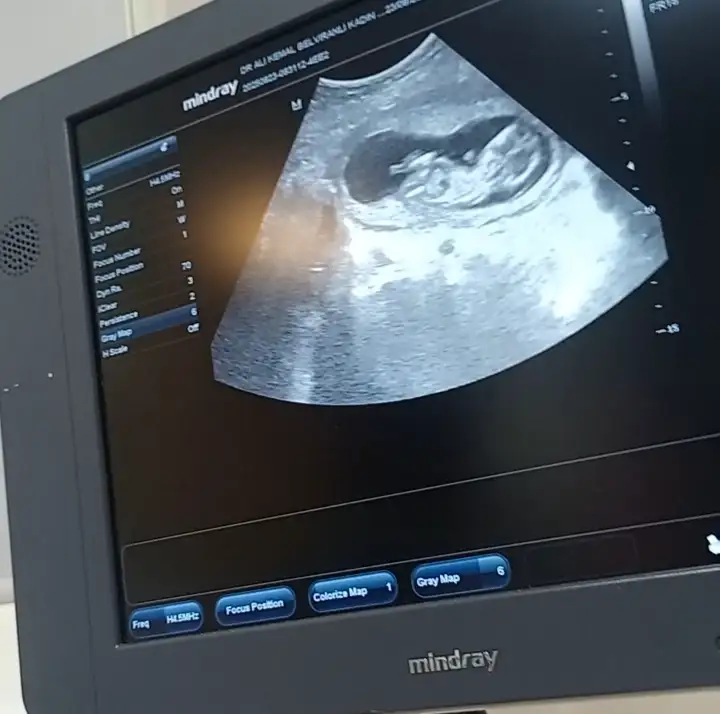

Erkek gibi :)12 hafta 3 günlük hamileyim cinsiyet tahmini yapar mısınız

Doktor birşey demedi mi hiç12 hafta 3 günlük hamileyim cinsiyet tahmini yapar mısınız

Benide yorumlar mısınKese fasulye gibi olunca erkek derler seninki yuvarlağımsı kız bence

Erkek geçti içimdenBenide yorumlar mısın

Ben erkek görüyorum gibiBenimkinede bakar misniz rica etsem